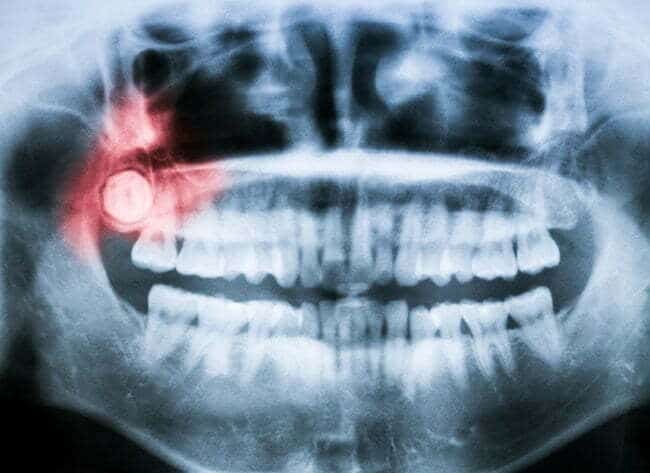

Before, during, and after the procedure, you can rest assured that you are in good hands. Our team will attentively listen to your concerns and patiently go through each step of the procedure with you, beginning with a physical examination and an X-ray screening to properly assess our treatment plan for you.